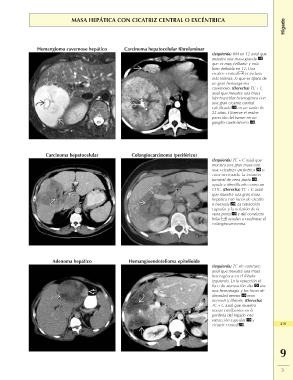

MASA HEPÁTICA CON CICATRIZ CENTRAL O EXCÉNTRICA Hígado

Hemangioma cavernoso hepático Carcinoma hepatocelular fibrolaminar (Izquierda) RM en T2 axial que

muestra una masa grande

que es muy brillante y está

bien definida en T2. Una

cicatriz central es incluso

más intensa, lo que es típico de

un gran hemangioma

cavernoso. (Derecha) TC + C

axial que muestra una masa

hipervascular heterogénea con

una gran cicatriz central

calcificada en un varón de

22 años. Observe el realce

parecido del tumor en un

ganglio cardiofrénico .

Carcinoma hepatocelular Colangiocarcinoma (periférico) (Izquierda) TC + C axial que

muestra una gran masa con

una «cicatriz» excéntrica o

zona necrosada. La invasión

tumoral de vena porta

ayuda a identificarlo como un

CHC. (Derecha) TC + C axial

que muestra una gran masa

hepática con focos de cicatriz

o necrosis . La retracción

capsular y la oclusión de la

vena porta y del conducto

biliar ayudan a confirmar el

colangiocarcinoma.

Adenoma hepático Hemangioendotelioma epitelioide (Izquierda) TC sin contraste

heterogénea en el lóbulo 219

izquierdo. En la resección el

foco de atenuación alta era

una hemorragia y los focos de

densidad menor eran

necrosis y fibrosis. (Derecha)

TC + C axial que muestra

masas confluentes en la

periferia del hígado con

retracción capsular y

cicatriz central .